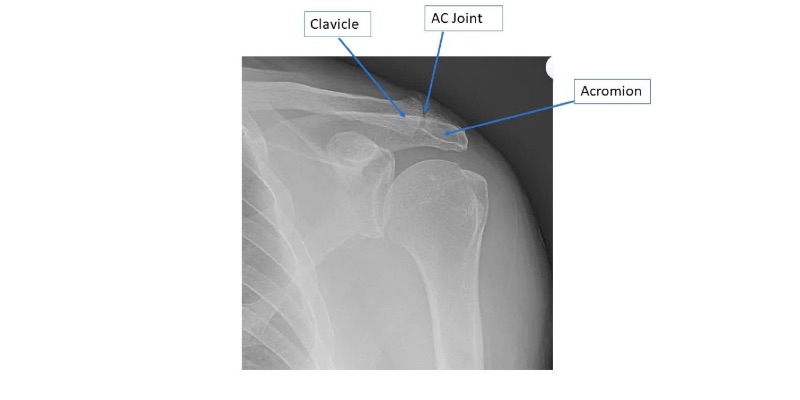

Distal clavicle or "AC" (acromioclavicular) arthritis results in pain over the shoulder, especially right on top of the shoulder with overhead and cross body maneuvers. Sometimes pain from AC arthritis can be present in addition to rotator cuff pain or a completely separate issue. Pain from the AC joint is usually quite distinct from rotator cuff pain but they can be confused. Arthritis of the AC joint is initially treated with physical therapy, NSAIDs, and cortisone injections. When these measures fail to help, a limited distal clavicle resection surgery can be performed to open up the space between the clavicle and acromion. This can be performed arthroscopically and requires only a few days of immobilization afterwards.

Shoulder radiographs demonstrating "AC" arthritis.